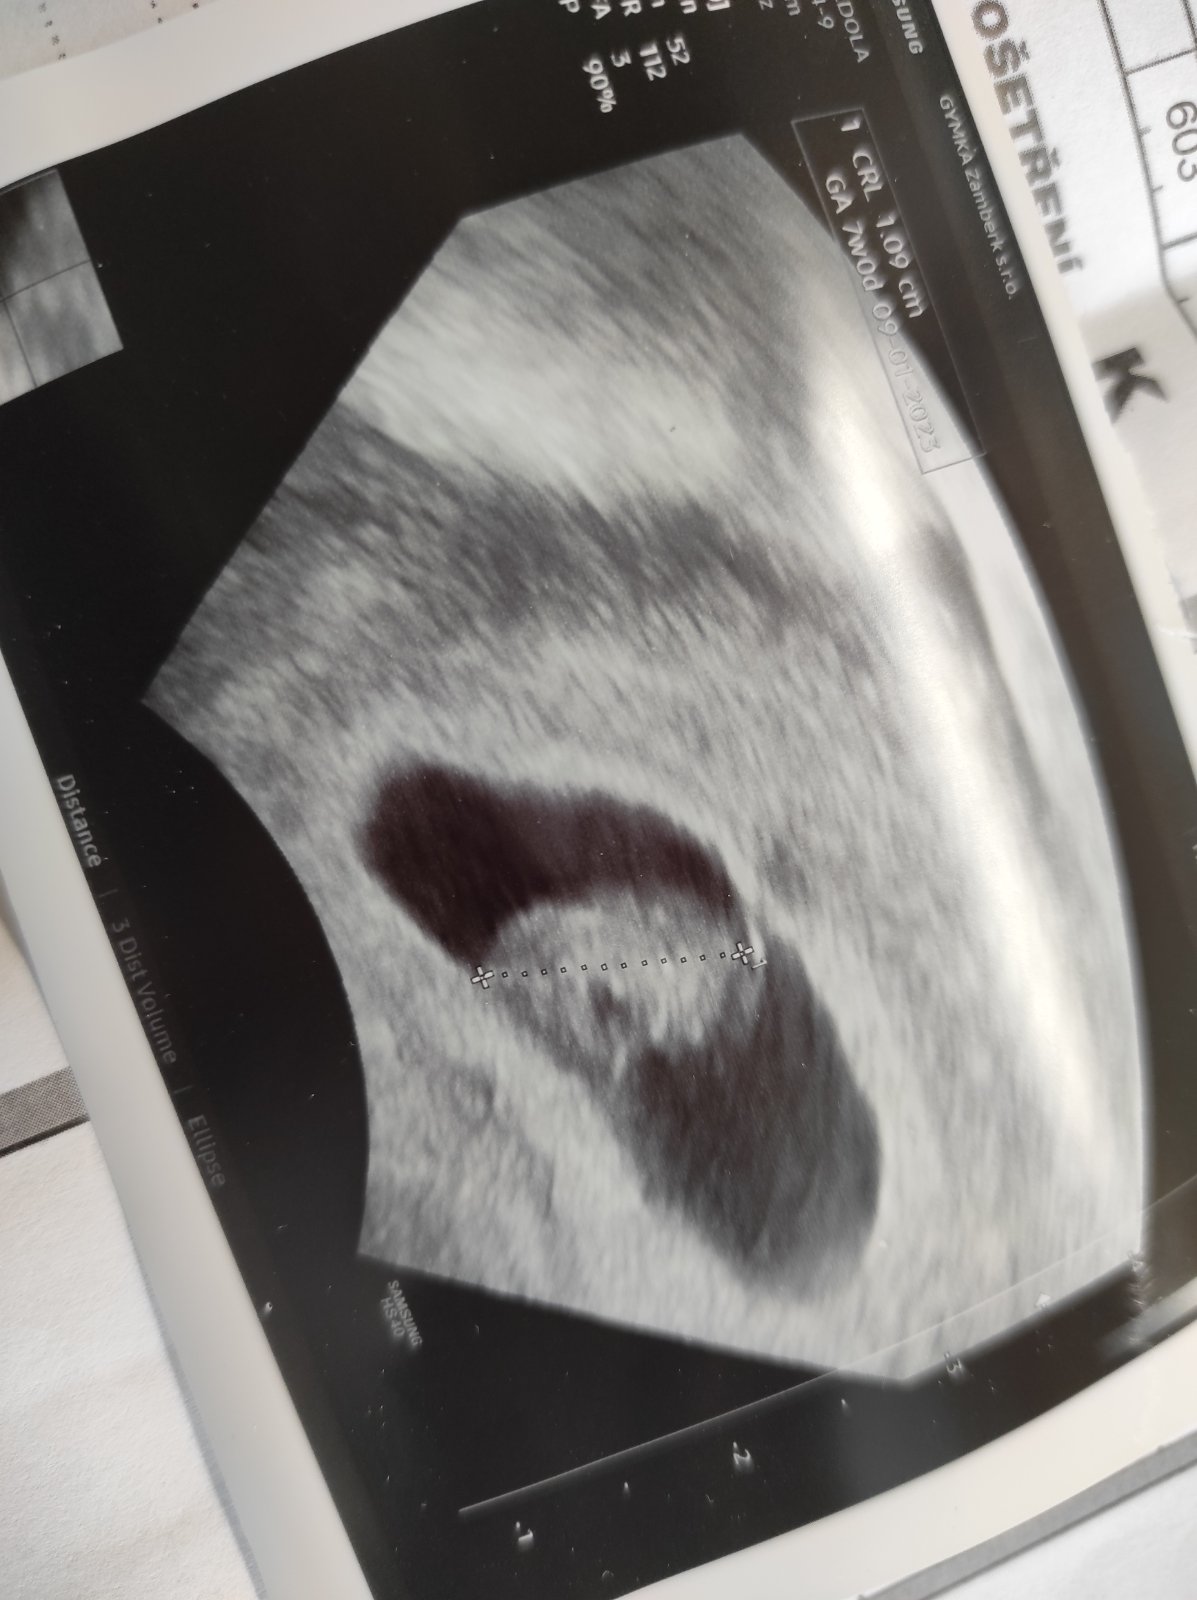

@ivetkafek18 já byla na kontrole teď v pondělí a všechno v pořádku byla jsem 7+0 což vycházelo jak podle ms tak i podle velikosti plodů a srdíčko bilo jako o závod ♥️♥️♥️

@karkulka1283 ahoj tak dnes jsem 6+2. Mam za sebou prvni sono. Srdicko bije krasne 🙂